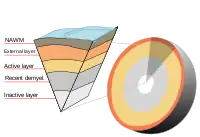

Lesions evolve from the Normal Appearing White Matter. In MTR-MRI, the apparent diffusion coefficient (ADCav) is a measure of water molecule motion. It can be seen that before the BBB breakdown, this coefficient increases until, at some point, the blood-brain barrier breaks down and immune cells enter the brain producing the lesion.[93]

According with the most recent (2009) research, an active lesion is composed of different layers:[94]

- NAWM border with the lesion: These areas contained activated microglia, antibodies binding to astrocytes, axons, oligodendrocytes and dendritic cells along blood vessels. No T or B cells are present.

- Lesion external layer: Number of oligodendrocyte cell bodies decreases. Remaining oligodendrocytes are sometimes swollen or dying. Myelin sheaths are still intact but swollen. Small increase in microglia and T cells.

- Active layer: Phagocytic demyelinating areas: There is myelin debris taken up by local microglia and phagocytes entering from the bloodstream. More T cells in these areas, and in the space adjacent to blood vessels.

- Recently demyelinated tissue: Tissues were full of myelin-containing phagocytes. Signs of early remyelination together with small numbers of oligodendrocytes. Large numbers of T cells, B cells, and other immune cells concentrated around blood vessels.

- Inactive layer: Again activated microglia and dendritic cells were also found around blood vessels.